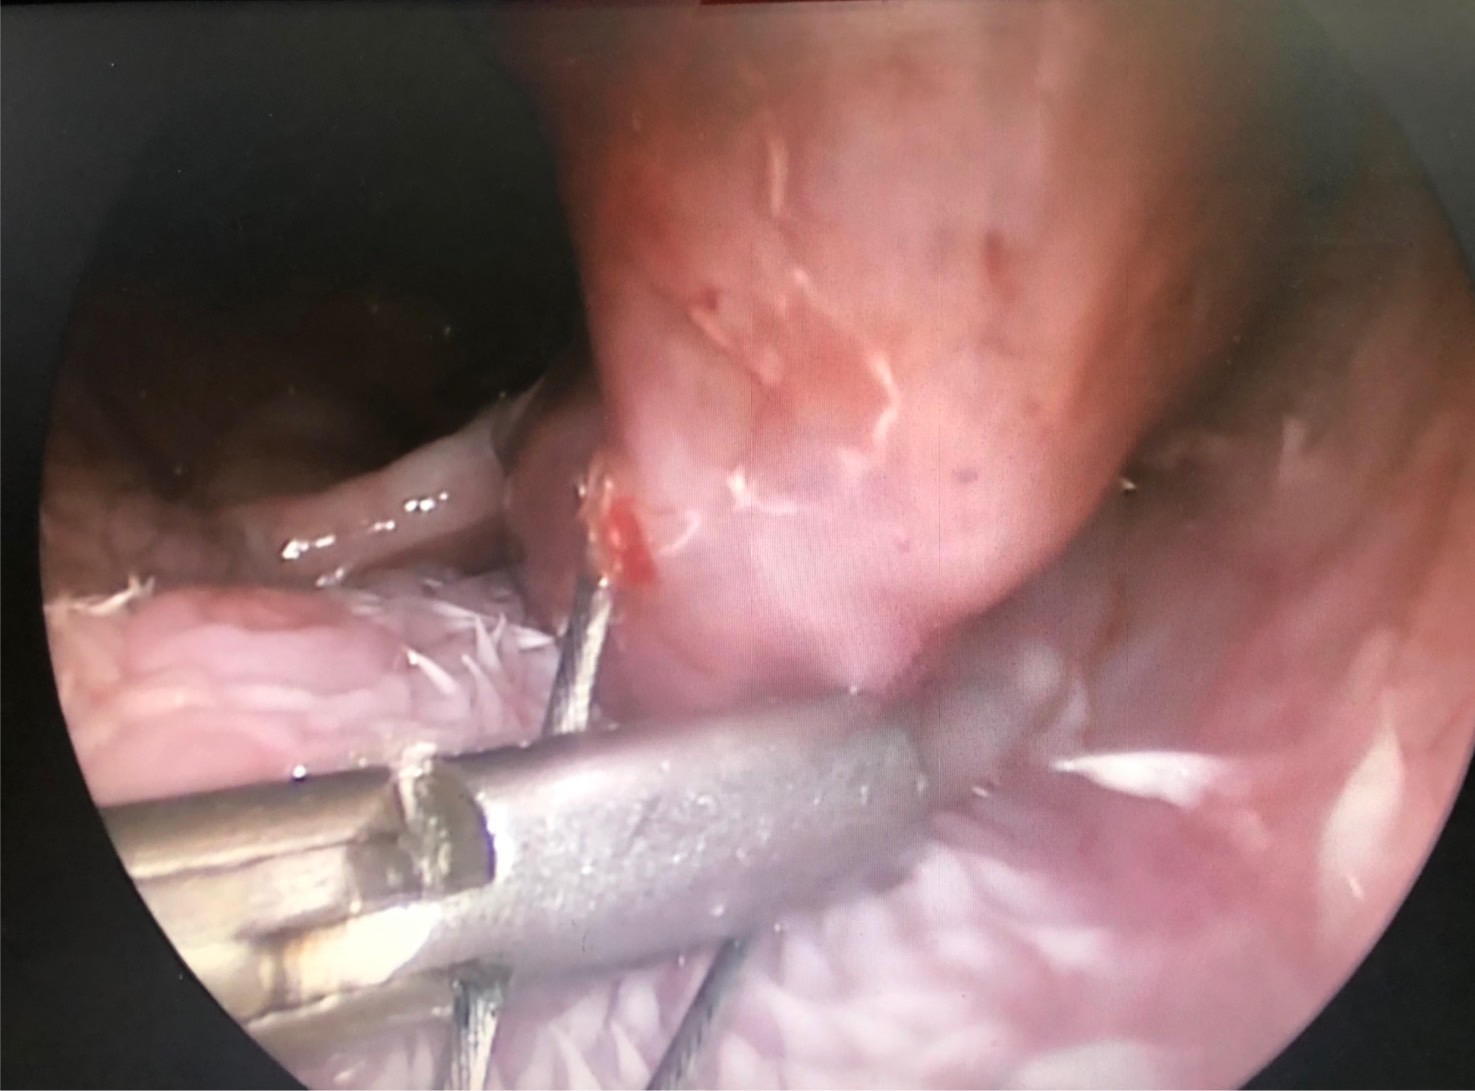

喉頭團塊 呼吸困難 急診

12歲未絕育男生 峽谷㹴主訴近幾周內喘 越來越嚴重 在附近看了四間不同間醫院都無法處理而轉來本院

初步懷疑呼吸道阻塞,安排電腦斷層掃描/內視鏡探查手術,精準定位病灶團塊的範圍,

利用內視鏡輔助套環套住團塊後經電燒將可見到範圍盡量切除乾淨。

同時將切除的團塊做病理切片。術後三個月到現在沒有症狀也沒有復發。

病理報告為嚴重、慢性活躍性、漿細胞及化膿性喉炎,伴隨肉芽組織生成及局部上皮細胞異型性,會厭旁團塊

這樣的病患如沒有及時處理,最後會因為呼吸困難而致死,需要完善的急診醫療團隊、住院照護團隊、

電腦斷層掃描、內視鏡手術團隊,缺一不可,這

樣的醫療資源並不多,很開心築心能夠及時讓狗狗恢復健康